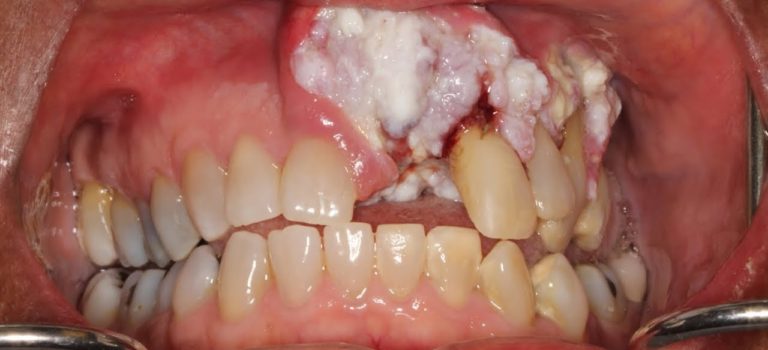

Dental Practice Financing For Dentists – Call BRT: 904-551-6090: Woman's Mouth Cancer Goes Ignored by Dentists for Years

Mouth cancer is an extremely serious condition that can sometimes be deadly. We were so happy to help save this woman’s life! A few years back, our patient …